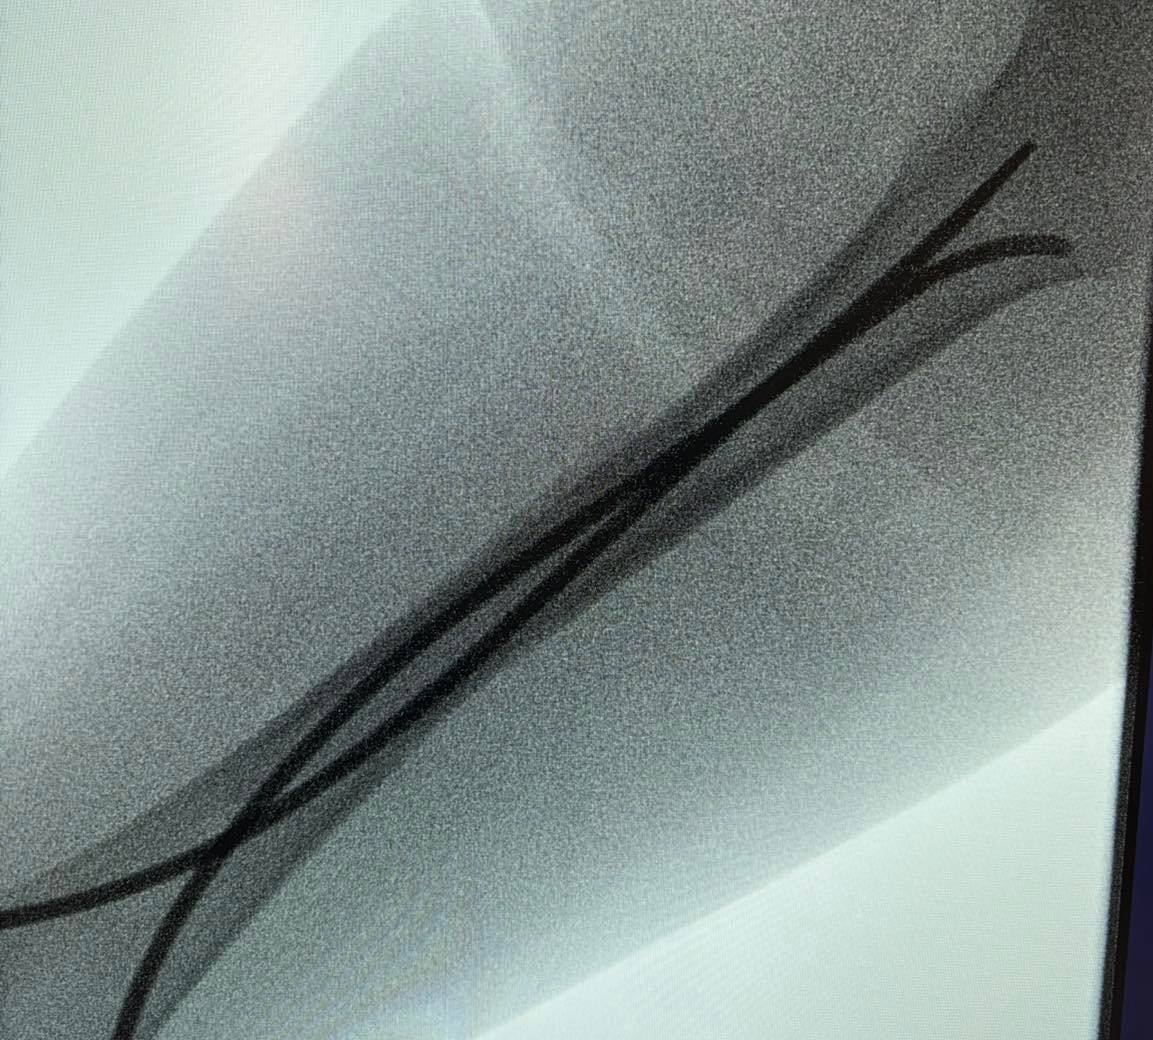

Інтрамедулярний остеосинтез – хірургічний метод лікування переломів, що дає можливість уникнути тривалого носіння гіпсових пов’язок та швидко реабілітуватися. Цей метод полягає у введенні в кістку гнучких титанових стержнів, які виконують функцію внутрішнього каркаса та фіксують кісткові відламки. Оперативне втручання проводять під рентген-контролем.

Наслідки падіння для 13-річного Максима – перелом стегнової кістки зі зміщенням і кісток гомілки.«Переломи дуже серйозні, – каже дитячий ортопед-травматолог Богдан Петерчук. – Попри це, завдяки інтрамедулярному остеосинтезу через два дні після операції Максим вже рухає ногою та швидко реабілітується. Оперативне втручання ми зробили через невеликі розрізи на стегні та гомілці».